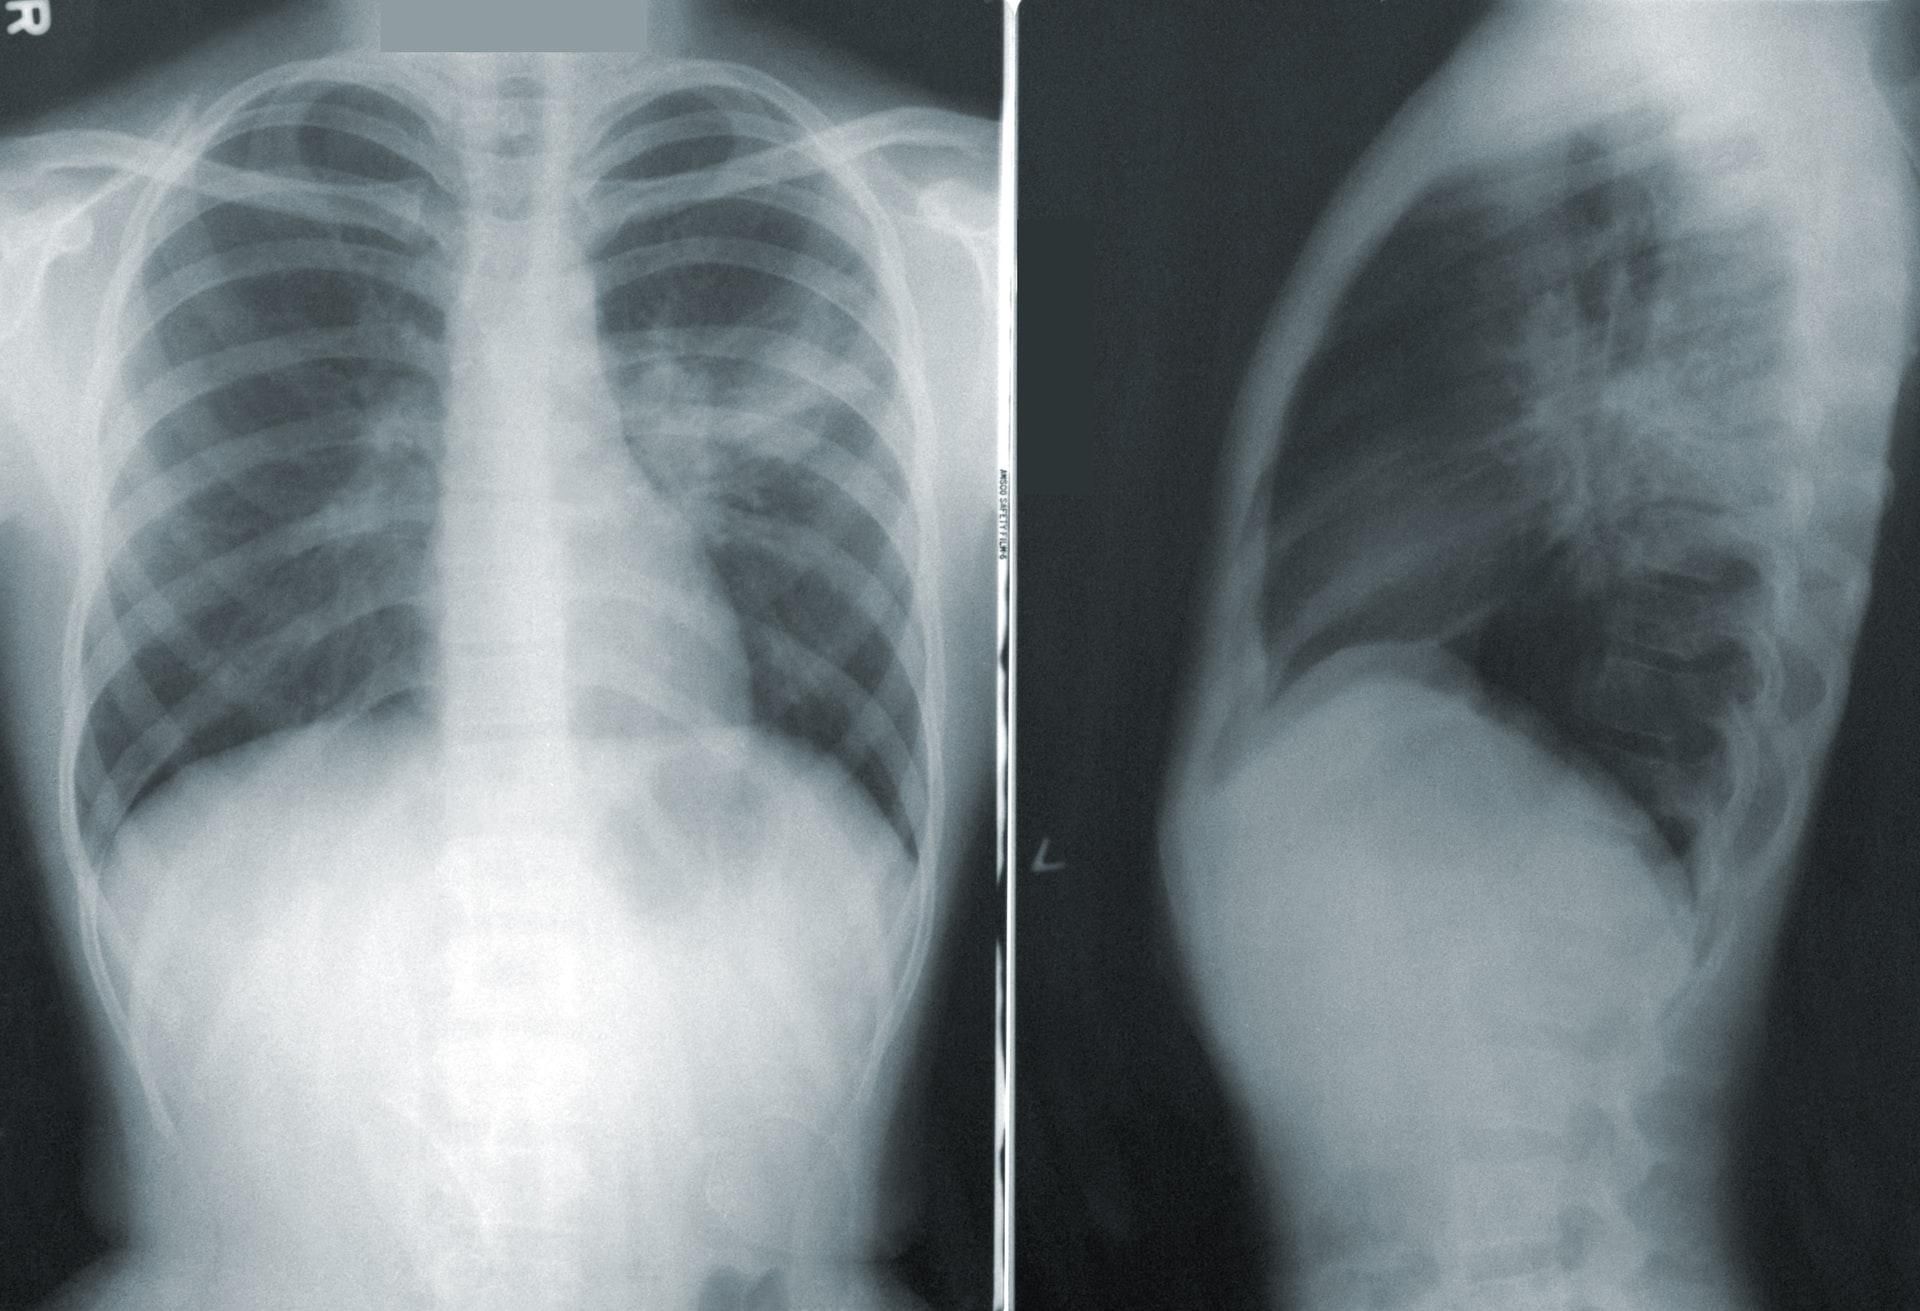

Однак звичайні методи обстеження (включаючи комп'ютерну та магнітно-резонансну томографії) часто не виявляють змін в роботі легень. Причини цих симптомів досі багато в чому залишаються загадкою.

У новому дослідженні брали участь дев'ять пацієнтів, які страждають від постковідного синдрому протягом не менше пів року після госпіталізації. Комп'ютерна томографія не виявила зміни в їхніх легенях, проте у них зберігалися задишка і втома.

Вчені провели їм обстеження за допомогою новітнього методу – магнітно-резонансної томографії з використанням гіперполяризованого ксенону (МРТ 129Xe). Ця технологія дозволяє дізнатися раніше недоступні дослідникам подробиці про функції легень.

Довготривале пошкодження легенів

На зображеннях, отриманих при МРТ 129Xe, вчені виявили порушення, невидимі для інших методів. У всіх відділах легень дев'яти пацієнтів спостерігалося утруднення проникнення кисню з альвеол в кров. Новітня технологія підтверджує факт пошкодження легень при довгому ковідові, дані отримані за її допомогою показують, що цей стан – не просто іпохондрія.